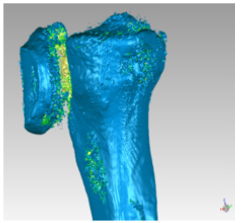

For shape optimization was used MeshLab. In (Figure 11) it is possible to observe only the representation of the tibia. The inaccuracies and irregularities mentioned above are clear here, especially in the upper part of the bone, near the knee. Furthermore, in the lower part of the image there is the indication relative to the number of faces that make the 3D surface (589951). To reduce the number of triangles that compose the mesh, it is important to eliminate vertices and faces included in the inner cavity of the model. These are useless for the purpose 3D printing. Their elimination simplifies the geometry making the 3D-printing phase faster and more effective. The Ambient Occlusion philter is applied which highlights the visible part. This function simulates a global diffuse illumination and colors the faces of the mesh according to a gray scale based on how much the single polygon is exposed to illumination. Once the philter is applied, we proceed selecting the bone inner material (highlighted in red in (Figure 12)) in order to simplify the model.

(Figure 13) shows the empty bone interior and the number of faces from which the optimized model is composed: 268349. Moreover, the elimination of small and isolated surfaces needs to be performed. Small Components function is used. This philter allows to choose the Ratio below which surfaces should be delated (Figure 14).At the end of the optimization process, mesh irregularities such as:

e. Disconnected zones: the mesh is composed of several disconnected zones are removed and the resulting clean surface will be used in the 3D printing process (Figure 14&15).